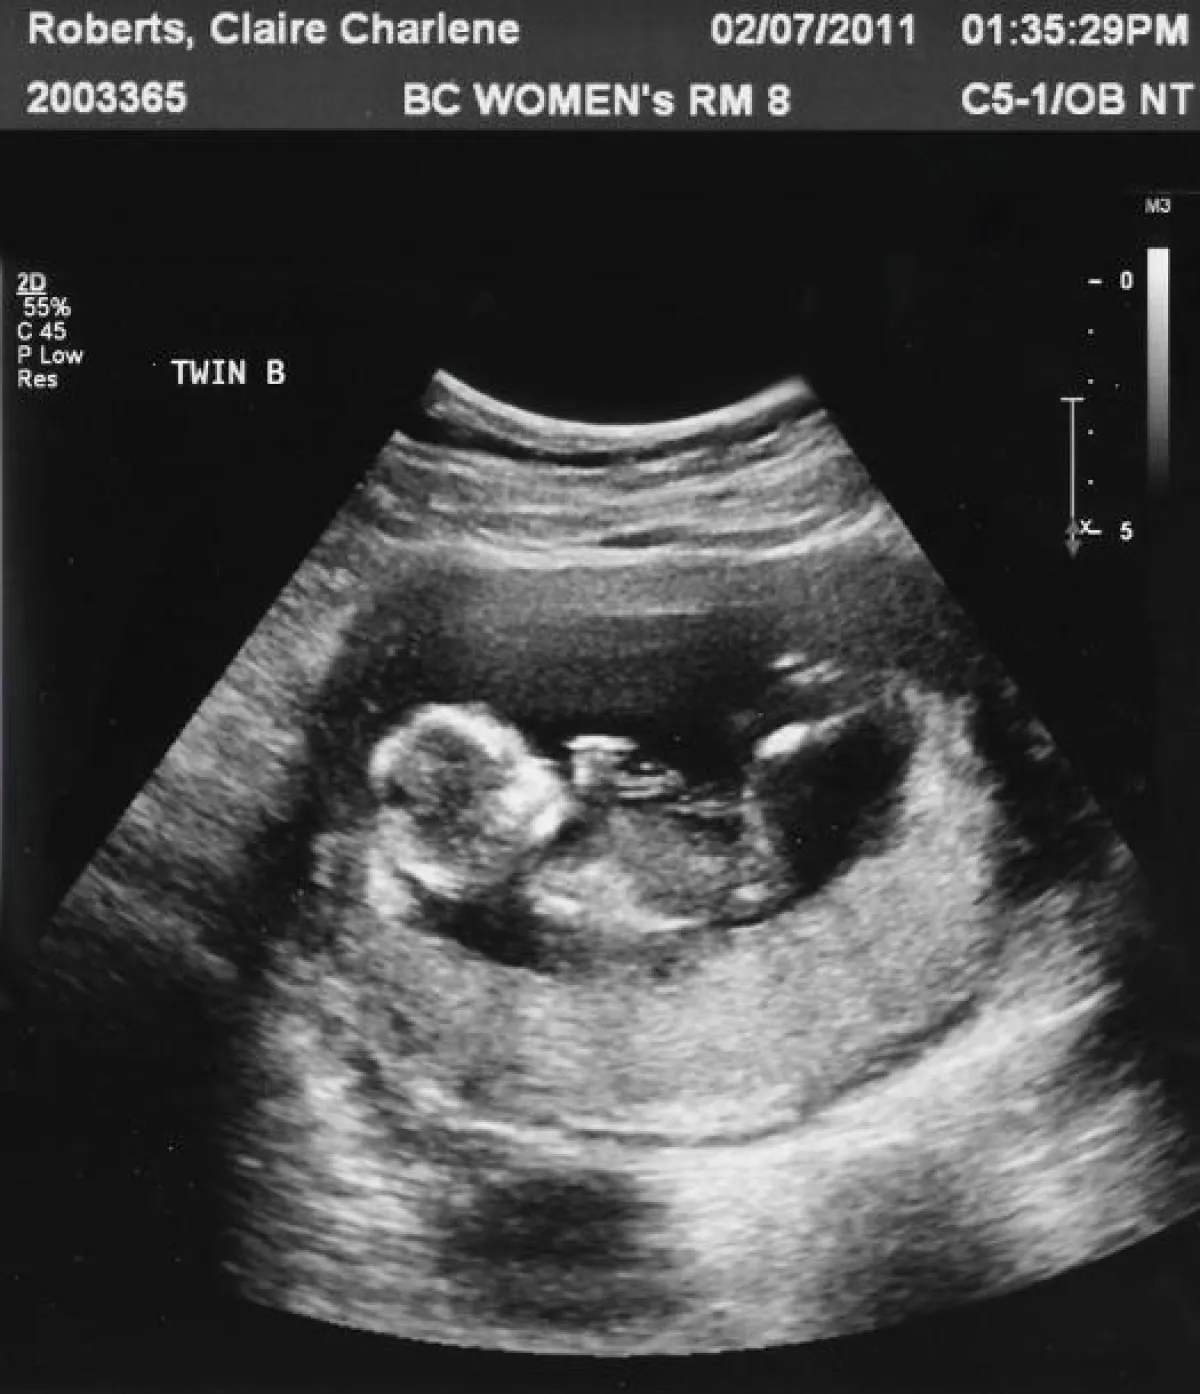

تلك اللحظة التي يذهب بها الزوجان إلى الطبيب لرؤية طفلهما في رحم الأم، تزدحم دائماً بالكثير من المشاعر، من بينها الحماسة والحب واللهفة للقاء الأول مع طفلهما، إلا أن زوجين أميركيين حدث معهما عكس ذلك تماماً، ووقعا تحت تأثير صدمة مرعبة للغاية، عندما ظهر الجنين بعينين مفتوحتين بشكل غريب، وشفاهٍ عليها ابتسامة عريضة ووجه غريب ومخيف؛ الأمر الذي دفع الأطباء إلى إطلاق اسم الطفلة الشريرة على الجنين، بعد اكتشافهم أنها فتاة.

صحيفة الديلي ميل البريطانية، نشرت أن سيدة أميركية، تُدعى إيانا كارينغتون، تعيش في مدينة ريتشموند بولاية فرجينيا، كانت خلال اليومين الماضيين قد ذهبت برفقة زوجها لإجراء فحص حمل لمعرفة جنس جنينها. وأُصيب الزوجان برعب كبير عندما شاهدا شكل الجنين بهذه الابتسامة المخيفة والعينين الواسعتين الغريبتين. حيث قال لهما الطبيب إن ما شاهده للتو حالة نادرة للغاية وفريدة من نوعها لم يرَ مثلها من قبل.

على الرغم من حالة الذعر التي مرت بها إيانا كارينغتون في أول الأمر، فإنها عادت لتطمئن وتهدأ، وأخذت صورة طفلتها المرعبة على محمل المزاح والسخرية، حيث نشرت صورة جنينها من فحص الحمل على صفحتها عبر مواقع التواصل الاجتماعي، وعلقت بأنه على الرغم من أن طفلتها تبدو شريرة ومخيفة، فإنها أحبتها، وإنها متحمسة جداً لولادتها ورؤيتها.

وتابعت السيدة الأميركية قائلة في منشورها: إن طبيبها النسائي الخاص، أخبرها أن طفلتها غير اعتيادية على الإطلاق؛ لأن معظم الأجنة يختبئون عن الكاميرات في حالة الفحص، بعكس طفلتها التي ذهبت نحوها مباشرة بهذا الوجه الغريب، والابتسامة العريضة.